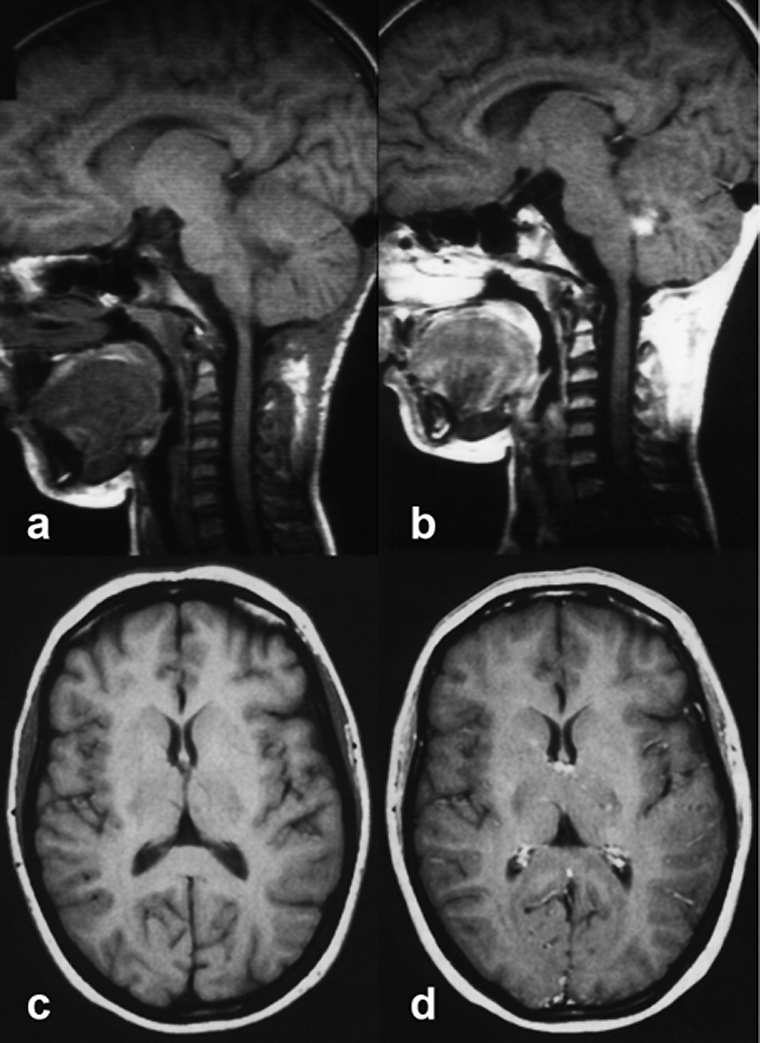

Figuras 13-10:

Top: Child with a small ependymoma.

(a) before contrast application, (b) after contrast application.

The contrast agent enhances the tumor, but also other highly vascularized parts of the head, among them the pituitary gland and infundibulum, bone marrow, nasal mu­co­sa, and blood vessels.

Bottom: Adult brain.

(c) before contrast application, (d) after contrast application.

Normal contrast enhancement in the cho­roid plexus and the superficial veins.